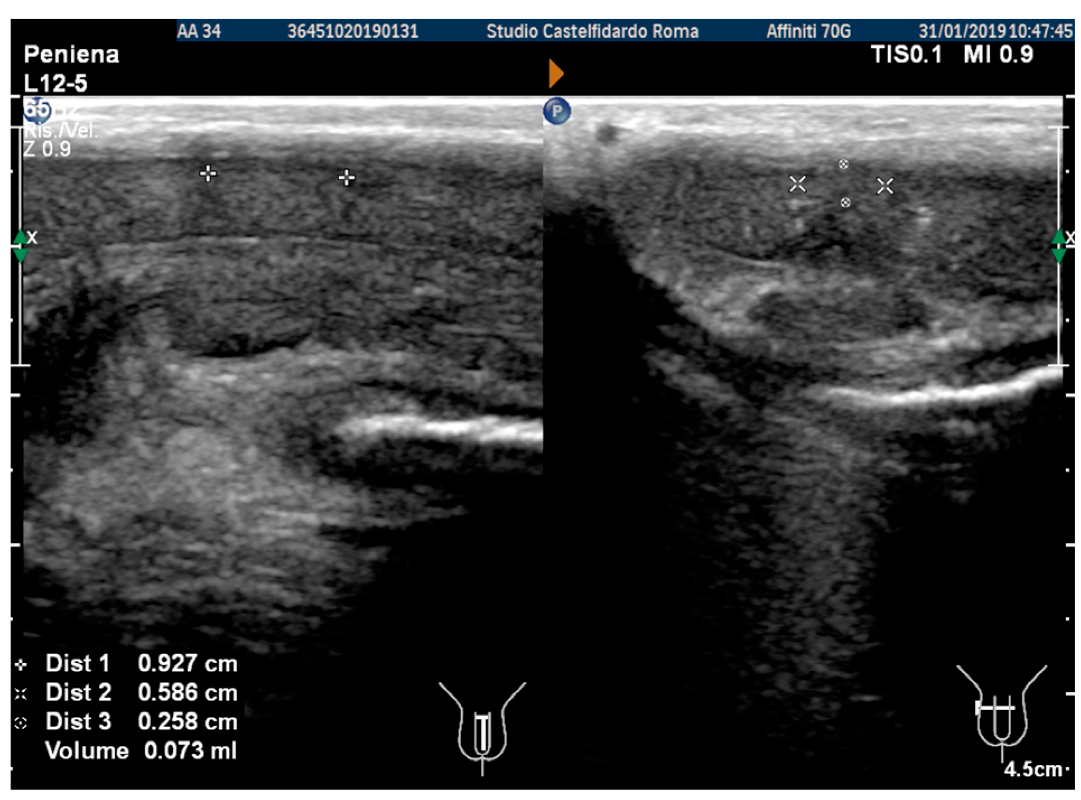

| 2 | 32 years | lichen sclerosus, chronic prostatitis | Proximal third | (A) 16.4 × 8.27 × 3.09 mm volume = 219 mm3 | (A) 10-degree left curvature | (A) score 3 | (A) score 26 | 2 years and 9 months | orally: Silymarin 400 mg + Ginkgo biloba 250 mg + Propolis 600 mg + Bilberry 160 mg + Vitamin E 800 IU/once a day, for 33 months. + topically: Propolis creme/twice a day/for 33 months. + peri-plaque penile injections: Pentoxifylline 100 mg (30 G needle) every 15 days for 6 months, and then monthly for 12 months, and then 1 injection every other month. for 12 months (total = 30 injections) |

| (B) No plaque detected | (B) None | (B) score 0 (after six months) | (B) score 28 | ||||||